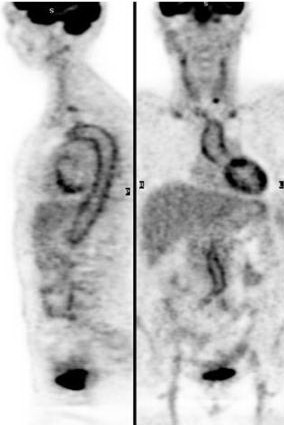

PET và PET/CT có tác dụng đặc biệt đối với ung thư. Các

phương pháp chẩn đoán hình ảnh như chụp cắt lớp vi tính (CT), cộng hưởng từ

(MRI), siêu âm… chỉ phát hiện và đánh giá được các tổn thương đã có những

thay đổi về cấu trúc, giải phẫu, mật độ của tổ chức. Vì vậy các phương pháp này

thường gặp khó khăn hoặc dễ bỏ sót các tổn thương có đường kính < 1cm. Trong

khi đó chụp hình toàn thân bằng PET và PET/CT có thể phát hiện các bất thường

về chuyển hoá, ghi được những hình ảnh bệnh lý sớm, còn nhỏ khi chưa có thay

đổi cấu trúc. Ở các bệnh nhân ung thư, sau phẫu trị, xạ trị, hoá trị các tổn

thương có thể bị biến dạng, thay đổi cấu trúc nên hình ảnh CT, MRI có nhiều hạn

chế trong việc xác định tổ chức còn sót, không phân biệt được tổ chức xơ hoá

với tái phát, di căn… Kỹ thuật PET cho phép khắc phục nhược điểm đó của CT và

MRI. Vì vậy độ nhạy, độ đặc hiệu để chẩn đoán ung thư của PET cao hơn rất nhiều

các phương pháp chẩn đoán hình ảnh khác. Do vậy hiệu quả kinh tế, xã hội của

PET và PET/CT là rất rõ rệt.